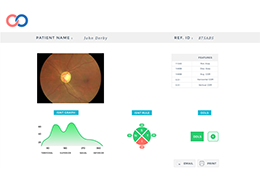

分析智能。

这些功能利用数字控制面板分析运营、业务和临床绩效。

使管理员能够跟踪关键参数,包括平均曝光率、拒绝的影像和探测器统计信息。

帮助确定需要改进的方面,支持为员工和部门制定适当的改进计划。